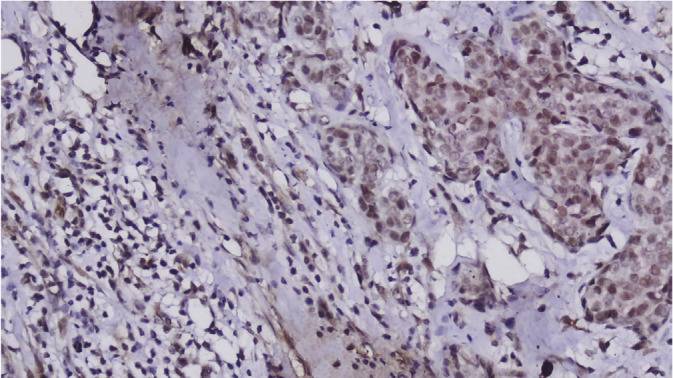

Materials and methods: The study included 282 patients with breast cancer. An in vitro diagnostic HMGB1 antibody was applied to the slides of tumor specimens.

Results: Overexpression of HMGB1 was found in tumor cells of 123 (43.6%) patients. HMGB1 was only expressed in the nucleus in most tumors (88.7%), while in 32 (11.3%) tumors HMBG1 expression was cytoplasmic and/or extracellular. Severe inflammatory infiltration of the peritumoral stroma was observed in 76 (27%) patients. There was a correlation between remarkable inflammatory cell infiltration in the tumor microenvironment and HMGB1 overexpression, regardless of the molecular subtype, as well as the extranuclear location of HMGB1 expression (p = 0.023). HMGB1 expression was not found to be associated with overall or disease-free survival. However, axillary lymph node metastasis was significantly more common in tumors with intense inflammation (p = 0.024).